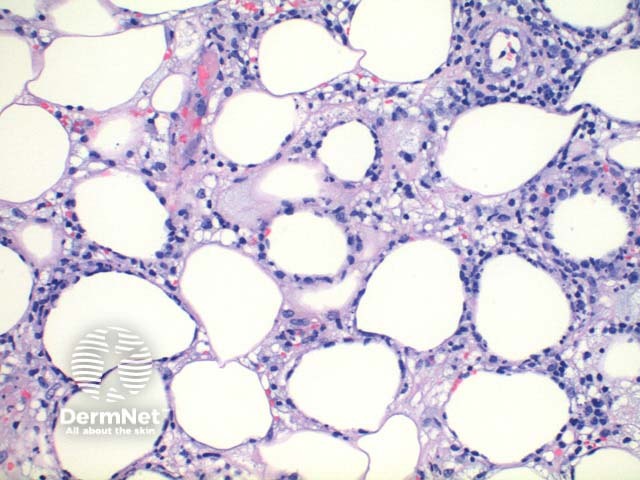

Scanning power view demonstrates lobular panniculitis (Figure 1). Relatively little dermal or epidermal involvement is seen (Figure 2). A dense infiltrate is seen predominantly within the fat lobules while some spillover into the septal panniculus may be seen (Figure 3). Germinal centre formation is rare. The infiltrate is predominantly lymphocytic with variable numbers of histiocytes engulfing nuclear debris (bean bag cells) and lipid (lipophages) (Figures 4 and 5). The lymphocytes demonstrate nuclear atypia and can be seen to characteristically rim the adipocytes (Figure 6).

Figure 3